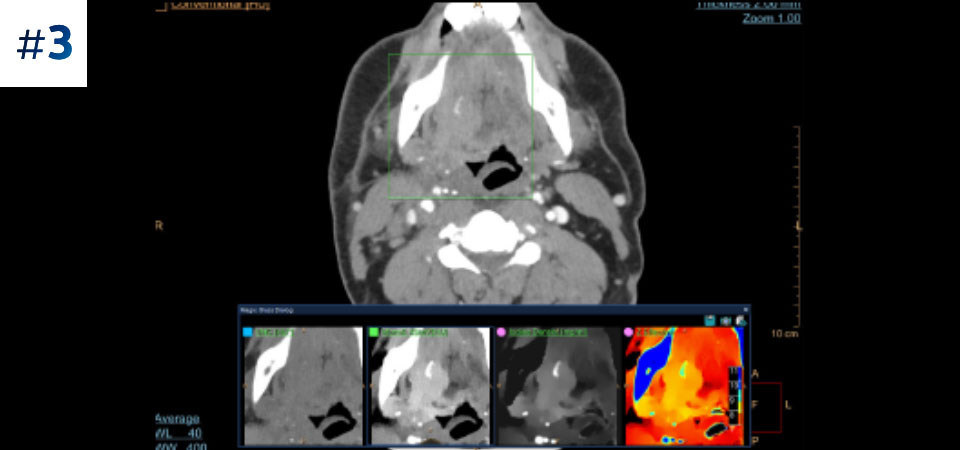

通常どおりにスキャン いつでもどの患者に対しても、1回の高速な低線量スキャンで標準データおよびスペクトラルデータを取得できます。

常に使用可能 スペクトラルデータは常に100%使用可能であり、検査結果はいつでも、オンデマンドだけでなく、レトロスペクティブに取得することもできます。

フォローアップ検査の削減 組織の特性評価と視覚化が改善されることにより、患者の検査が最適でなかった場合や、偶発病変が見つかった場合に、フォローアップスキャンを行う必要性が低減される可能性があります。

さまざまな患者タイプ 小児患者から肥満患者まで、幅広い患者タイプにメリットがあります。